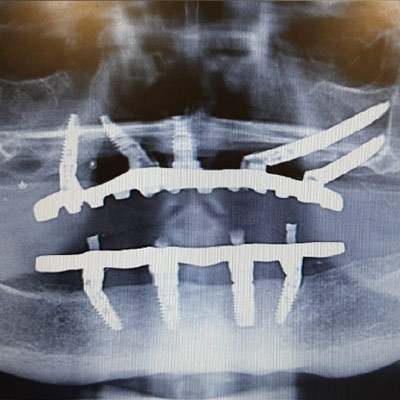

Chirurgia Extramascellare

Cosa fare quando i processi alveolari sono estremamente atrofici: in questo modulo affrontiamo programmazione e realizzazione di riabilitazioni con supporti nasali, zigomatici e pterigoidei.

La sfida della moderna implantologia avanzata: denti fissi in qualsiasi situazione.